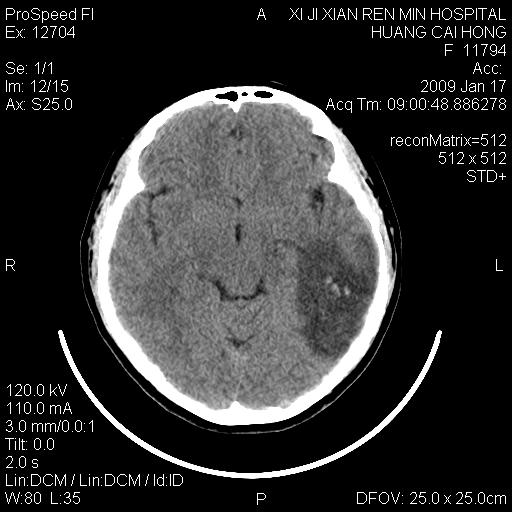

以下是引用zbp537在2009-1-19 13:54:00的发言:[br]首先考虑脑炎。[br]诊断依据:[br]1、患者较年轻。[br]2、有感冒病史。[br]3、左侧颞枕叶这么大一片低密度影,占位征象却不明显,不符合肿瘤特征,其内的高密度影为出血灶。

以下是引用xiaoniu在2009-1-19 13:29:00的发言:[br]左侧颞叶三角形低密度影,占位效应不明显,其内点片样高密都影,青少年患者,首先考虑:少突胶质瘤。因为有感冒病史,不能除外感染的可能。

以下是引用黑白光影在2009-1-19 16:44:00的发言:[br]首选“感染”伴点状出血!次选:少突胶质瘤!

以下是引用卜一在2009-1-19 15:13:00的发言:[br]首选“感染”伴点状出血!次选:少突胶质瘤!